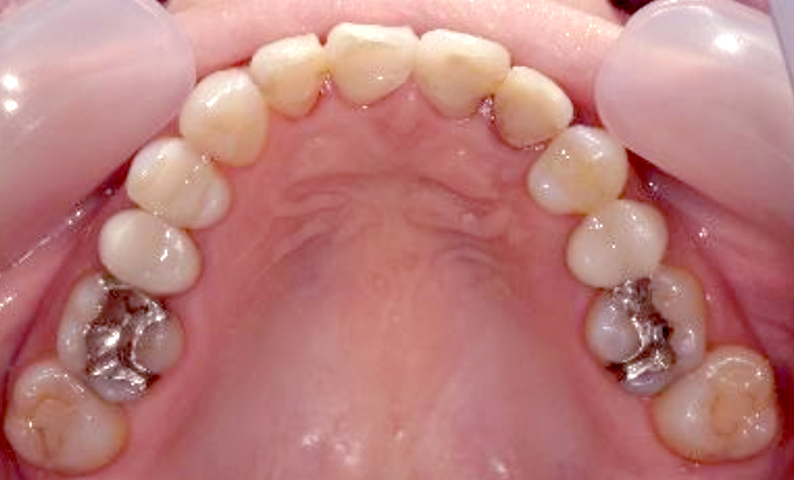

症例_022 上下顎の部分矯正

治療期間:9ヶ月金額:51万円+税女性前歯のガタガタ八重歯

| Before | After |